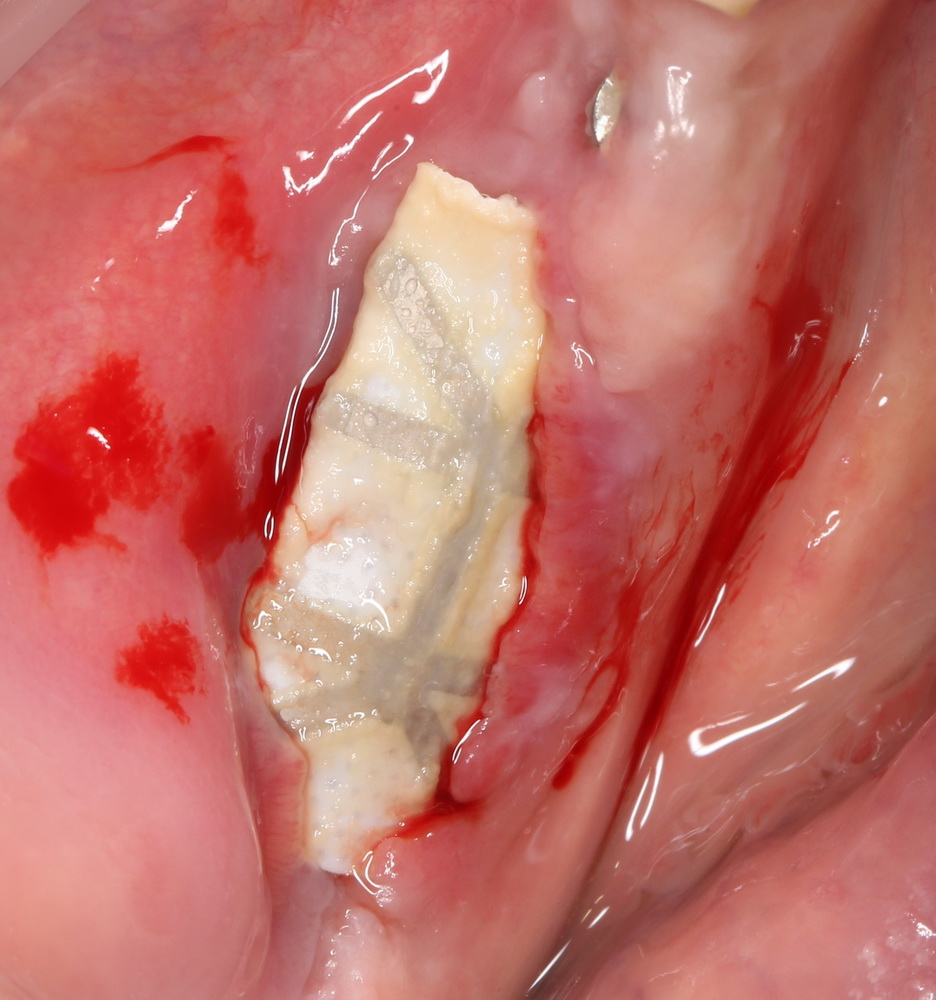

Что же касается нерезорбируемых мембран… Было дело, работал с Gore-Tex (дорого, очень дорого), титановыми сетками (заколебался потом доставать) и тефлоновыми Cytoplast:

результат:

или